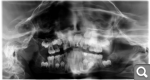

Анна Жол Опубликовано 25 июня, 2019 Поделиться Опубликовано 25 июня, 2019 Здравствуйте! Недавно делали пантоортограмму сыну 8 лет, в связи с тем что передний верхний молочный резец никак не хочет меняться на коренной. Диагностика показала, что зуб находится в десне в перевернутом состоянии! В 5 лет была травма- удар по верхней челюсти. Зубы остались на месте, но один был перебит в районе корня, куда в дальнейшем был вставлен штифт (на данный момент этот зуб уже удален). Наблюдаемся у ортодонта в поликлинике, носим пластинку для выравнивания соседнего зуба и расширяем челюсть, чтоб зубы не сдвигались на пустое место. По поводу перспектив доктор конкретики не дает. Что делать в нашей ситуации? Есть ли возможность вытащить зуб из десны с помощью брекетов или имплантация в 18 лет? И если не трудно объясните причины, почему он перевернулся, это так был заложено изначально, или последствия травмы? Есть томограмма в эл. виде, не знаю как загрузить сюда Ссылка на комментарий